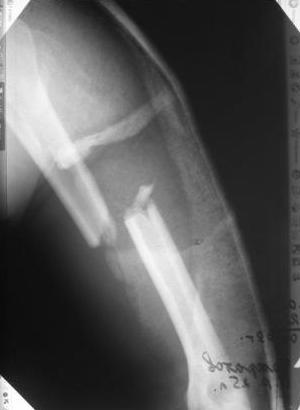

Перелом нестабильный, тактика - если позволяет сосояние больной, оперативное лечение. Как пример см. ниже, можно без скобы - стяжки с ЭПФ.

Представленный способ, функциональный, данная больная в качестве внешней иммобиллизации в течение 3-х недель полльзовалась косыночной повязкой, востановление функции плеча полное. Правда травма изолированная, но операция выполнялась через три недели после травмы, тот час после обращения ко мне - иногородняя.